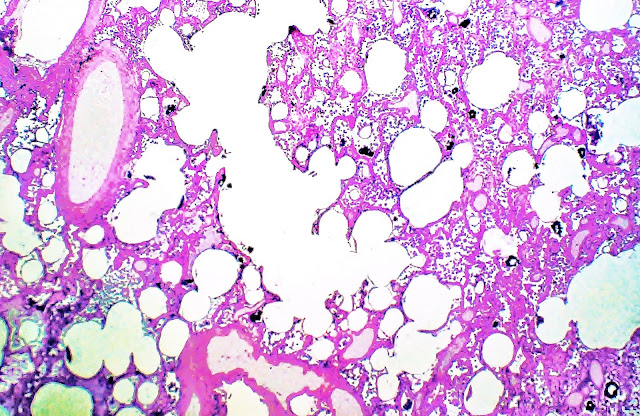

Fig. 10.- Pulmón.Tricrómico de Masson.

A pequeño aumento muestra áreas de edema y de hemorragia y la presencia de material particulado en algunos espacios alveolares. Algunos alveolos muestran una especie de revestimiento laminar seudomembranoso. Prof.Garfia.A